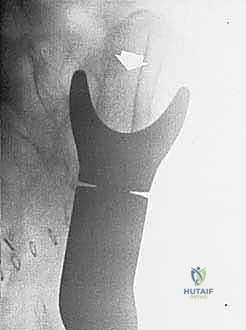

كسور لوح الكتف: تشخيص دقيق، علاج فعال، وتعافٍ أسرع!